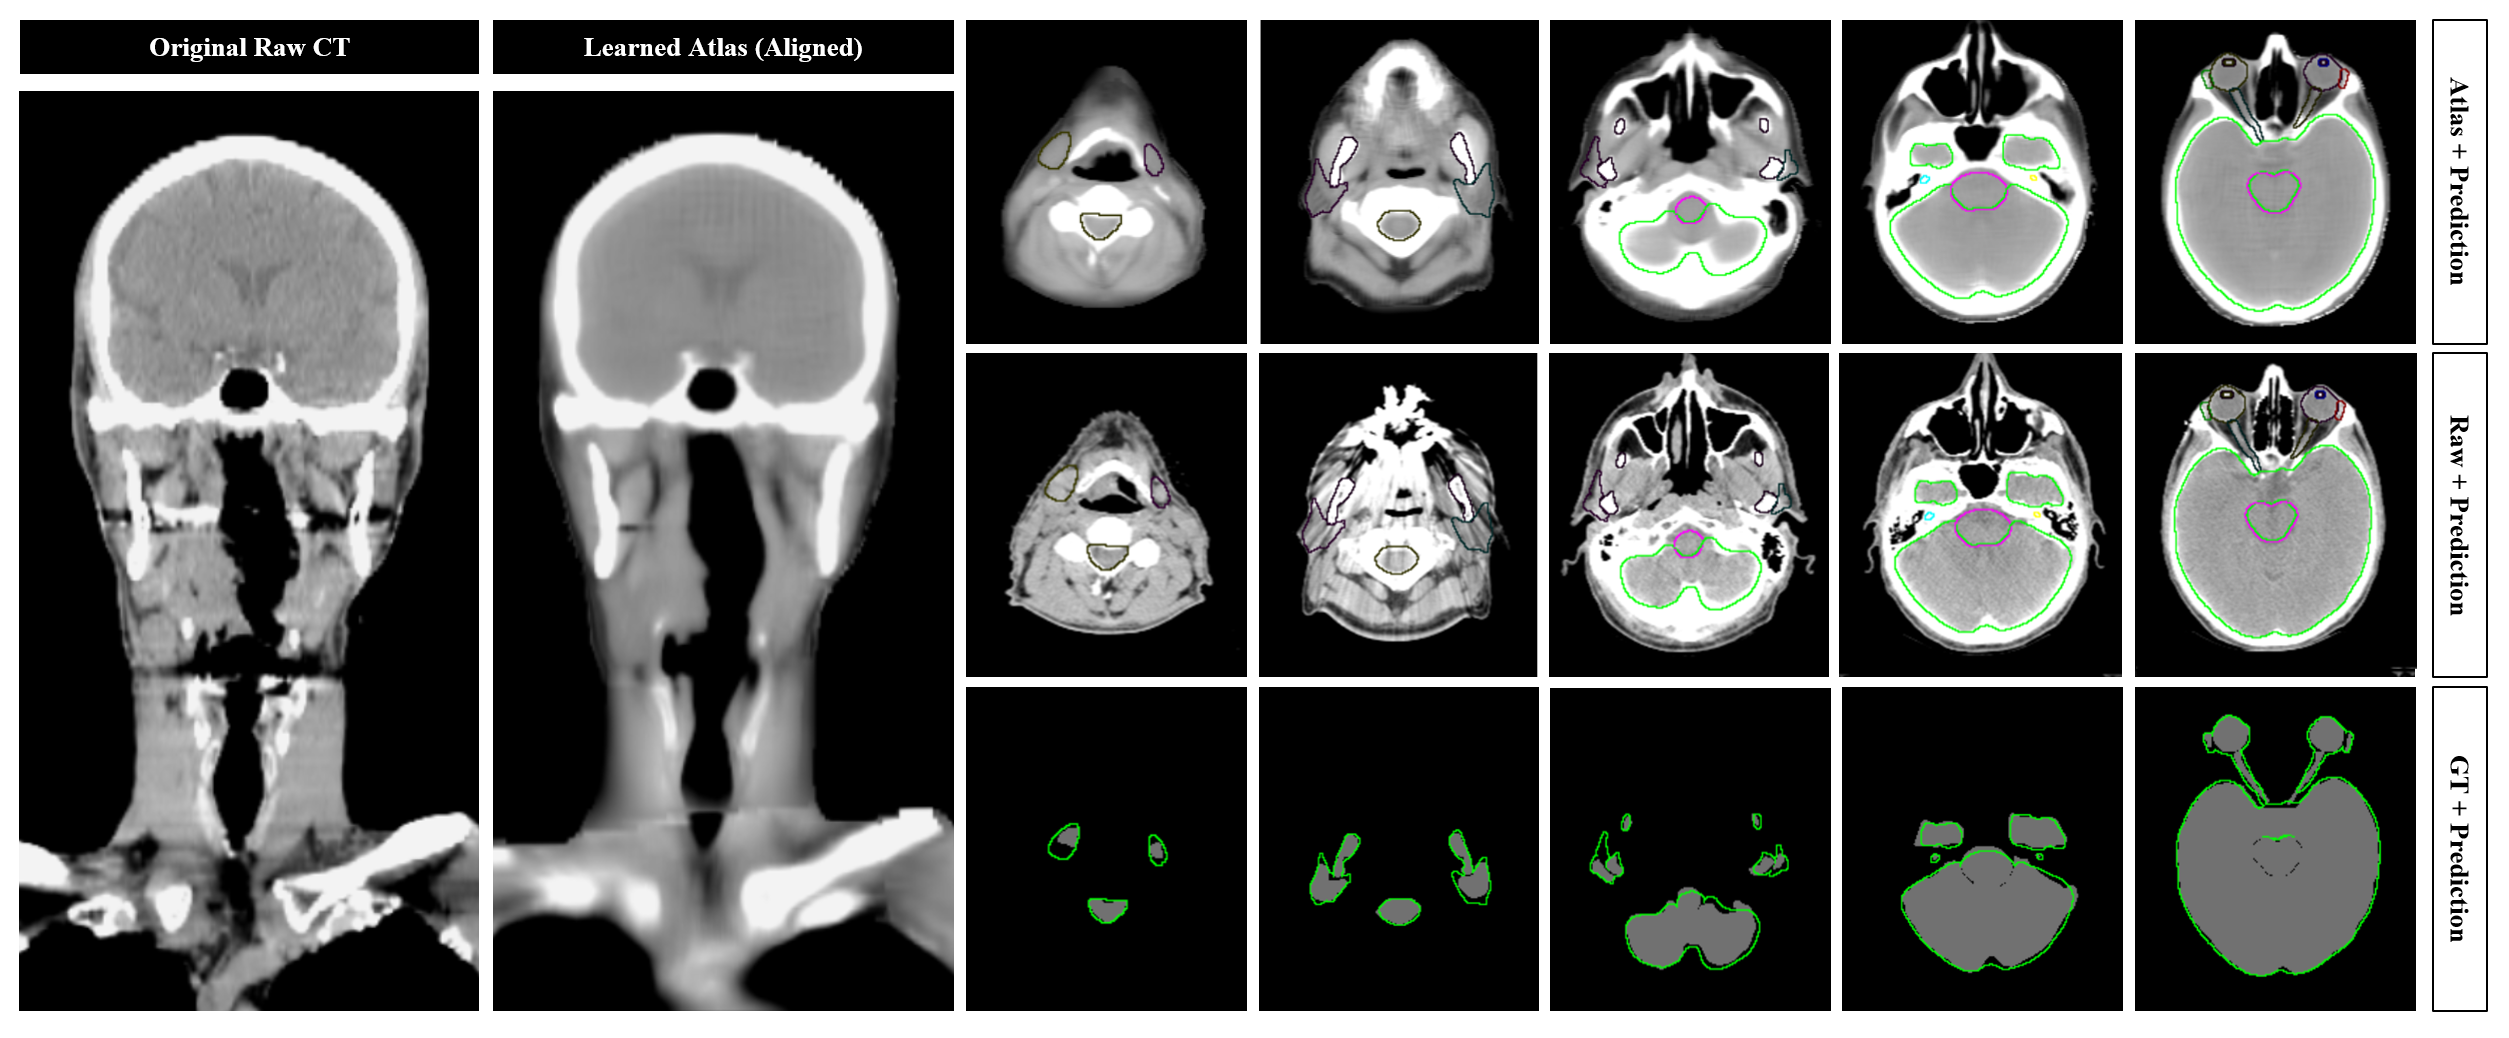

Refer to caption

Figure 4: One-Shot Segmentation (Head-and-Neck Organ-at-Risk Cohort). A forward-pass of the DeepATLAS model labels every discrete position in an exam with a coordinate matching its underlying anatomy. To visually approximate the predicted anatomy at each location, the generated coordinate map may be used to project the learned atlas (a reconstruction of the learned coordinate space) to any given exam. As shown in the left two panels, the aligned atlas reconstruction exhibits high-fidelity correlation with raw CT data, suggesting the ability to generalize across many anatomic structures including those not directly evaluated in this experiment. In the right panels, single-shot segmentation masks are shown overlaid on the aligned atlas (top panels), raw CT data (middle panels), and ground-truth (bottom panels). In this example, segmentation masks are shown for the lens, orbit, optic nerve, lacrimal gland, cochlea, mandible, parotid gland, submandibular gland, brain, and brainstem.